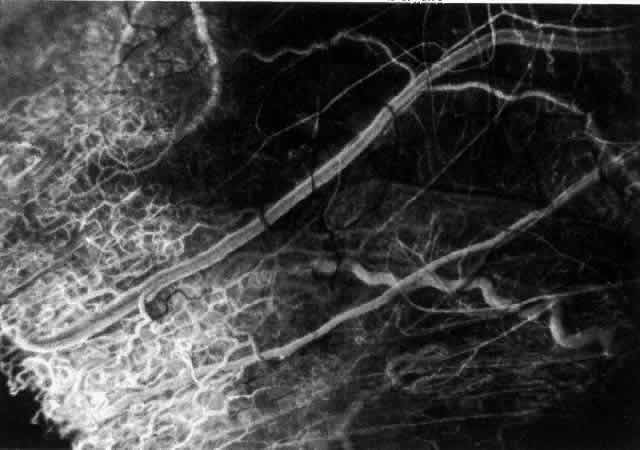

ARTERIAL PHASE Anterior Episcleral Arterial Circle The anterior ciliary arteries run radially toward the limbus within Tenon's capsule, giving few, if any, branches until they reach the anterior part of the globe. Their positions are very variable, and they do not always follow the rectus muscles. They bifurcate 2 to 5 mm behind the limbus, and each division runs forward and circumferentially to anastomose with a branch from an adjacent artery. This results in an anterior episcleral arterial circle (Figs. 3 through 5). The divisions of the anterior ciliary arteries are typically superficial at their origins but run deeper at their anastomoses. They occasionally dip too deep to be seen in fluorescein angiograms (Fig. 6).

From the anterior episcleral arterial circle, four distinct circulations are supplied: episcleral, anterior conjunctival, limbal, and iris. Episcleral Circulation Immediately after their origin by bifurcation of the anterior ciliary arteries, the contributions to the anterior episcleral circle divide again to give recurrent branches that run posteriorly and subdivide to form a netlike episcleral plexus (see Fig. 5; Fig.7). The variability of the positioning of the anterior ciliary arteries inevitably leaves large areas of episclera far from such an arterial supply (see Figs. 4, 6, and 7). These areas receive other posterior branches from the episcleral circle. Where the circle runs deep within the sclera, such branches appear as isolated perforating vessels (see Fig. 6). They fill very shortly after the episcleral circle, and they also divide repeatedly as they run posteriorly.

Anterior Conjunctival Circulation Throughout their superficial course, the arteries of the episcleral circle give off fine loops that run forward into the limbal reflection of the conjunctiva before curving back radially and dividing to form the lacework of the anterior conjunctival capillary plexus (see Fig. 2). The delicate column of blood within the anterior conjunctival loops may be punctuated by a string of individual erythrocytes, suggesting that the lumen is approximately 12 μm in diameter. Anterior conjunctival loops may also arise from perforating posterior branches of the episcleral circle (see Fig. 6). The anterior conjunctival circulation, supplied by the anterior ciliary arteries, always fills before the posterior conjunctival circulation, which is derived from the posterior tarsal vessels (see Figs. 4 and 5). The watershed zone between these sources can fill very late (see Fig. 5). However, anterior conjunctival loops do sometimes anastomose with arteries of similar caliber derived from the posterior tarsal circulation. Limbal Arcades Limbal arcades are supplied by anterior branches from the episcleral circle. Their origins are often shared with those of the anterior conjunctival loops, and, where the circle runs deep, they too are derived from the perforating posterior branches. They often fill very late during a normal angiogram (see Fig. 7). The limbal capillary loops never leak fluorescein, even during high-dose angiograms, suggesting that their endothelial cells are united by tight junctions. Iris Vessels The first flush of fluorescein within the anterior episcleral arterial circle always coincides with filling of the radial arterioles of the iris. It may be implied from this that the iris receives a major supply from the anterior ciliary circulation (see Fig. 6). In some angiograms, the iris circulation appears to derive directly from the episcleral circle. This raises the possibility that the “major circle of the iris” and the episcleral arterial circle are less distinct entities than has hitherto been presumed. VENOUS PHASE Anterior ciliary veins accompany the arteries, but there is no well-organized venous ring corresponding to the anterior episcleral arterial circle. The posterior episcleral branches of the arterial circle are paralleled by centripetal venules, and looping anterior conjunctival venules are interspersed between the arterioles (see Figs. 4 and 5). The posterior conjunctiva drains back into the tarsal circulation. CAPILLARY PHASE The episcleral capillary net is often difficult to discern below the more prominent conjunctival circulation. It is most clearly seen when the conjunctival circulation fills late for anatomic or pathologic reasons. The anterior conjunctival capillary plexus forms an interlacing network between the anterior conjunctival arterioles. Perfusion of the watershed zone that separates the territories supplied by the anterior ciliary and posterior tarsal systems may be delayed by as much as 15 seconds after first flush (see Figs. 5 and 7). However, this region is often crossed by arteriolar anastomoses between the two circulations, and the destination of venous blood is irrespective of its origin from the anterior ciliary or posterior tarsal circulations. |